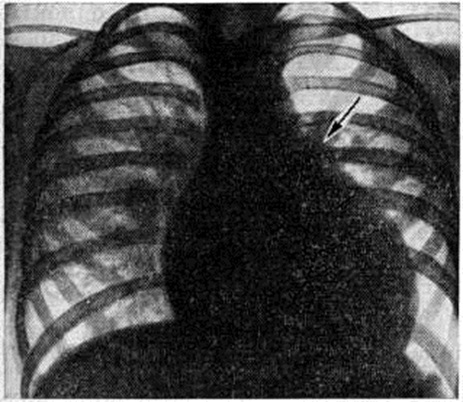

Рентгенограмма грудной клетки больного при полной форме атриовентрикулярного канала (прямая проекция): контуры сердца округлой формы за счёт увеличения правых и левых отделов.

Определяемое расщепление II тона с усилением лёгочного компонента связано с гиперволемией малого круга и блокадой правой ножки пучка Гиса. На ЭКГ — отклонение электрической оси сердца влево. На ФКГ над верхушкой сердца и в четвёртом межреберье слева регистрируется интенсивный систолический шум, связанный с регургитацией крови из желудочков и сбросом крови из левого желудочка в правый. Эхокардиограмма регистрирует необычные движения передней створки митрального клапана, иногда её расщепление и наличие промежутка между ней и межжелудочковой перегородкой. Рентгенологически определяется умеренная или значительная кардиомегалия и дилатация лёгочного ствола (рисунок 7).